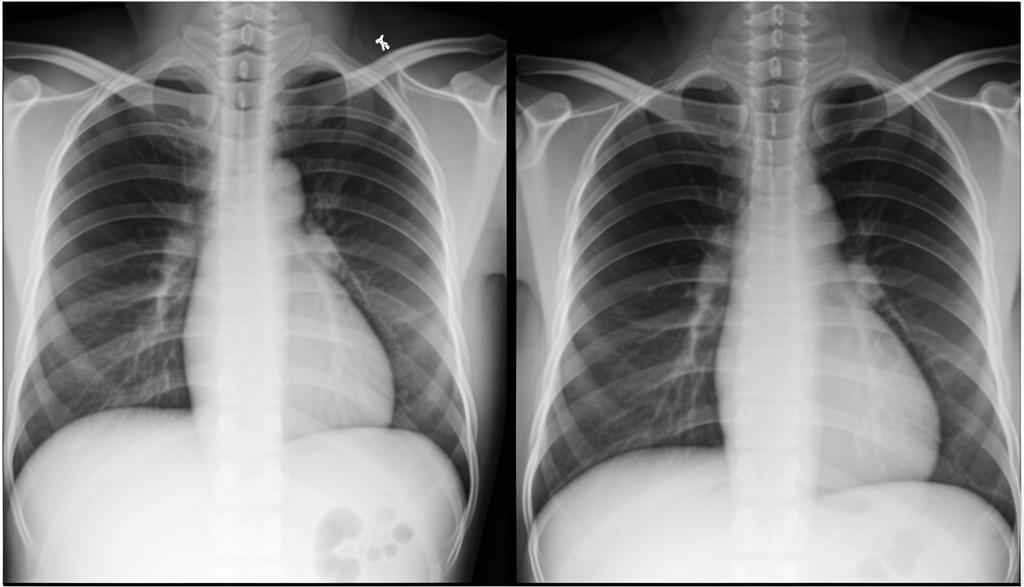

Chest X-Ray Dataset for Pneumonia Detection

A comprehensive dataset of chest X-ray images for pneumonia detection, collected from Mbarara Region...

1250 files

2.5 GB